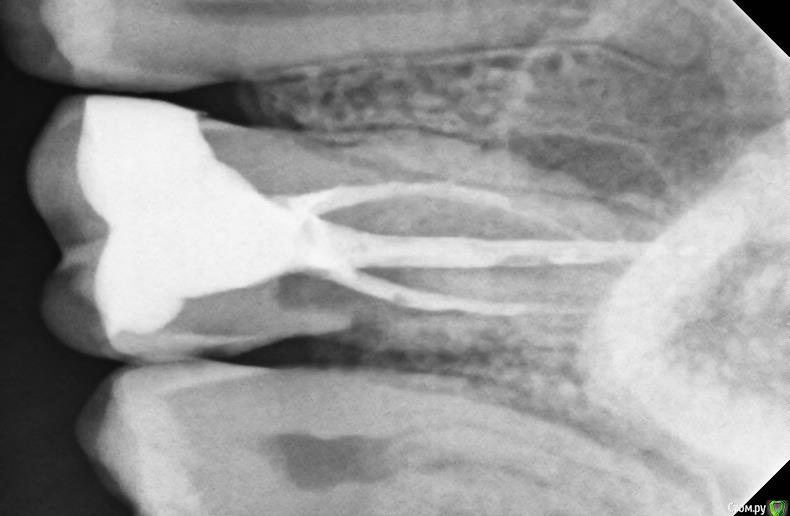

sole13 Опубликовано 18 декабря, 2017 Поделиться Опубликовано 18 декабря, 2017 Уважаемые врачи,посмотрите, пожалуйста, снимок зуба Очень хочется сохранить зуб 7 лет назад 26 зуб -удалили нервы, залечили зуб 2 года назад сильные нарастающие боли и несколько врачей сказали что зуб не подлежит восстановлению, т к воспаление на уровне кости (?), пропила антибиотики, один врач взялся без гарантии перелечивать каналы: 2 перелечил, а при прохождении третьего пошла кровь и он сказал, что корень был препарирован при удалении нервов ранее=> поэтому ситуация с воспалением, месяца 3-4 я проходила с пастой на основе кальция(?) зуб не болел, потом запломбировали на протяжении этих 2 лет при простывании 2 раза в год болит зуб, иногда пью антибиотики иногда сам прорывает гной через десну и боль проходит. 1. реально ли сохранить такой зуб? как?2. темное на снимке - это разреженная кость ( идет на убыль из-за воспаления)? можно ли как-то удалить воспаленные ткани и восстановить кость за счет искусственного материала?3. не могу понять по фотографиям 2015 и 2017 годов: есть ли положительная динамика? спасибо!2017 год 2015 год Ссылка на комментарий